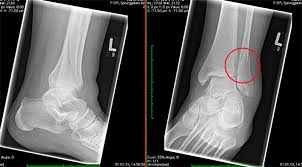

Fraktur oberhalb der verletzen Syndesmose Membrana interossea häufig auch rupturiert Die Maisonneuve-Fraktur wird als Sonderform der Sprunggelenksfraktur auch als Weber C klassifiziert. This normally takes approximately 6 weeks to heal. Die Weber-Klassifikation eine Methode zur Beschreibung von Sprunggelenksfrakturen.

KLASIFIKASI FRAKTUR WEBER Drsimon ponco septiono f Weber A Garis fraktur berada dibawah syndemiosis thibiofibularis f Weber B Garis fraktur berada setinggi syndemiosis thibiofibularis f Weber C Garis fraktur berada diatas syndemiosis thibiofibularis f. Weber C Fraktur immer Weber A- und Weber B- Frakturen mit. Many translated example sentences containing Weber c Fraktur English-German dictionary and search engine for English translations.

Weber C Fraktur. Neben der Weber C Fraktur gibt es auch noch die Fraktur der Klasse A und B. Was ist eine Weber-C-Fraktur. DayZ sa well kit DayZ Expansion Building Kits - YouTub. Verschobenem Bruch dislozierte Fraktur undoder. It has a role in determining treatment. Weber C Fraktur. Look up the French to German translation of weber c fraktur in the PONS online dictionary. The Weber ankle fracture classification or Danis-Weber classification is a simple system for classification of lateral malleolar fractures relating to the level of the fracture in relation to the ankle joint specifically the distal tibiofibular syndesmosis.